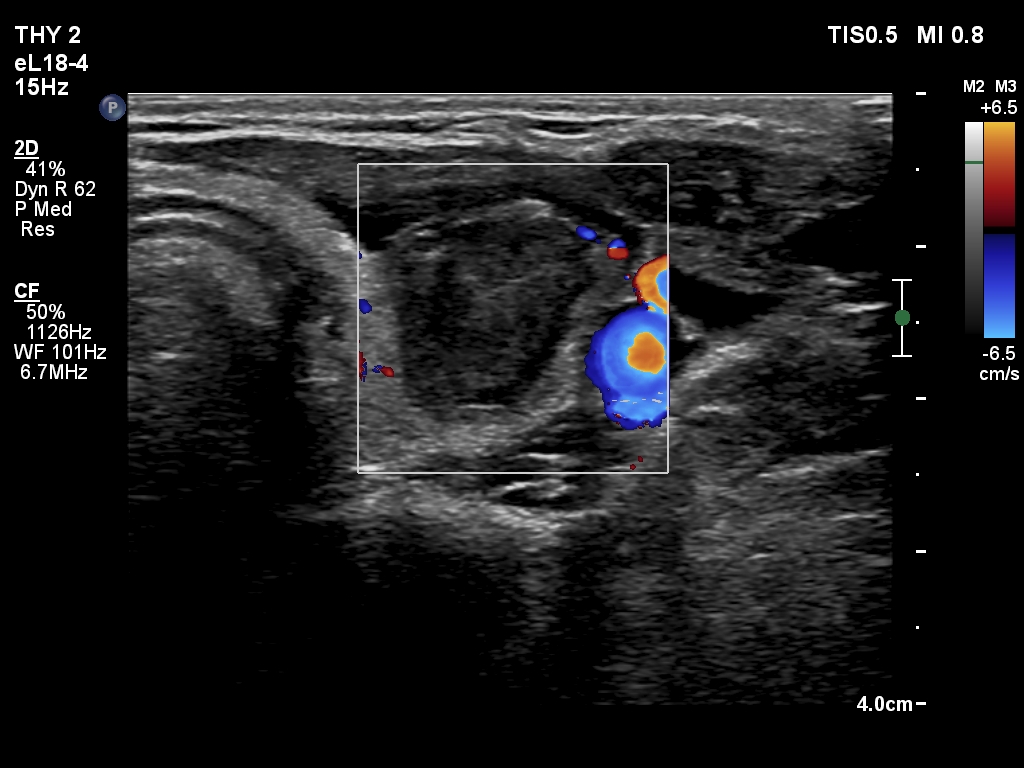

Second session of sclerotherapy (fourth row of images):

Clinical presentation. The patient had no complaints.

Ultrasonography. A minimally hypoechoic-echonormal mass has appeared within the nodule. By compression, we could detect flow of the mass.

This time 2.5 mL fluid was removed and 4.8 mL ethanol was injected. At the end of the session the patient felt a straining pain which lasted for half minute.

The echogenicity of the cystic portion has changed after the first session, a seemingly solid area has appeared. However, by compressing the nodule, this mass presented flow, which proved that this was in fact, at least in part, fluid.